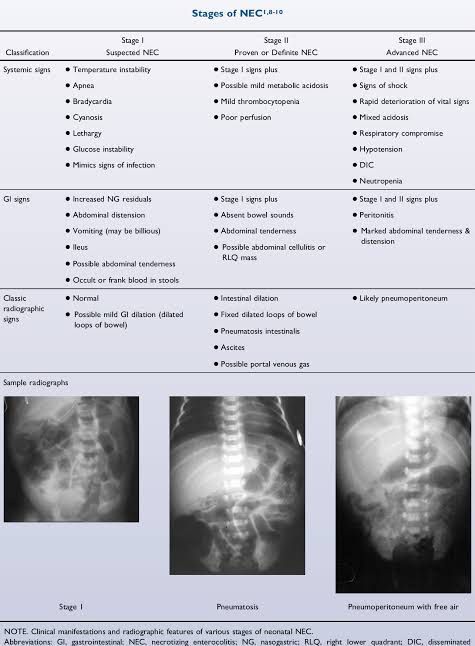

Stages of necrotizing enterocolitis

Necrotizing Enterocolitis